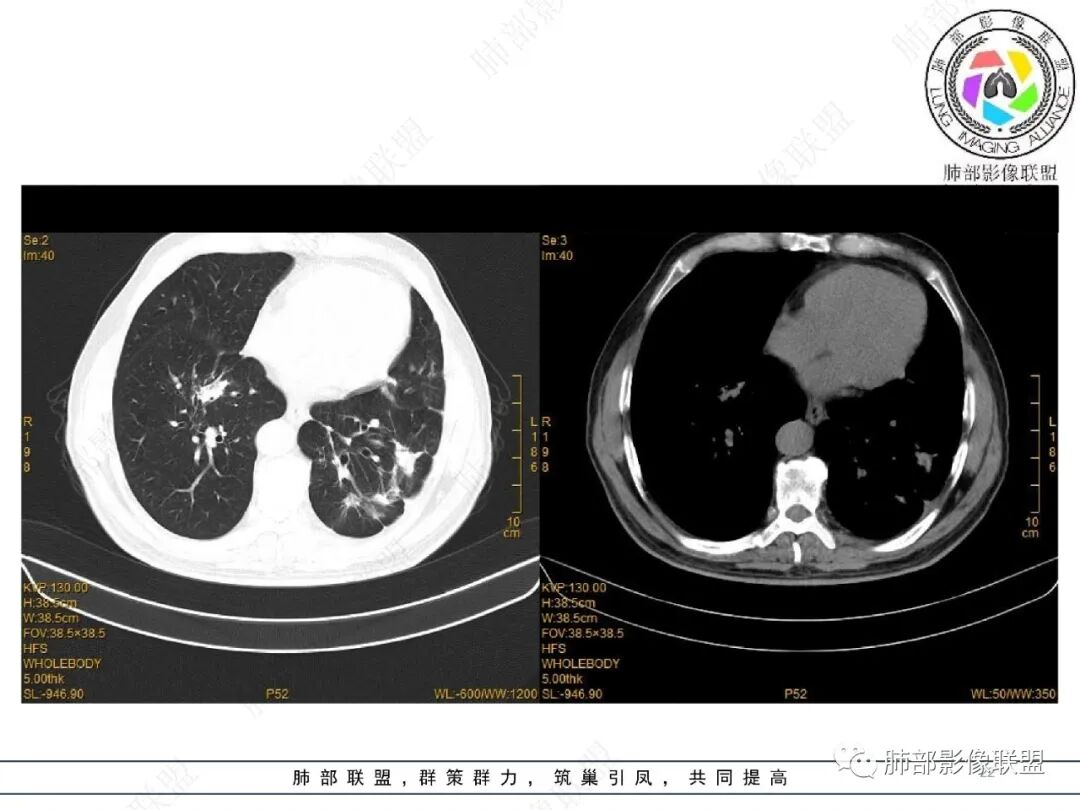

2022.2.17CT显示两肺中内带多发结节影、斑片影、条索影,部分病灶侧向融合与胸膜平行。部分病灶沿着支气管血管束分布、其内支气管稍扩张。部分病灶呈反晕征。大部分病灶边界显示清晰,部分病灶周围可见边界不清的GGO。2022.4.12CT显示两肺中内带多发结节影、条索状、条带状高密度影,边界收缩平直凹陷,大部分病灶沿着支气管血管束分布,亦有位于胸膜下侧向融合与胸膜平行的病灶。总体与第一次CT对比两肺病灶明显吸收。